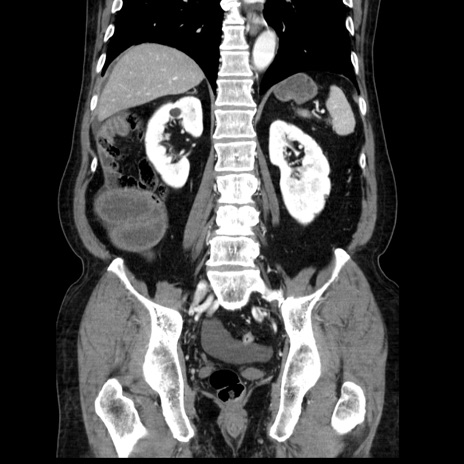

症例30(冠状断像)

【症例】80歳代男性

【主訴】臍周囲痛

【現病歴】約6時間前から臍下部痛が出現。次第に腹部膨隆・背部痛も生じてきたため来院。背部痛の場所は変化しない。

【身体所見】意識清明、BT 36.3℃、BP  131/87mmHg、P 87bpm、SpO2 100%(RA)、臍周囲自発痛・圧痛あり、反跳痛なし、自発痛部位に一致して板状硬あり、腹部膨隆、腸雑音減弱、CVA tenderness両側陰性。

【データ】WBC 19600、CRP 0.33